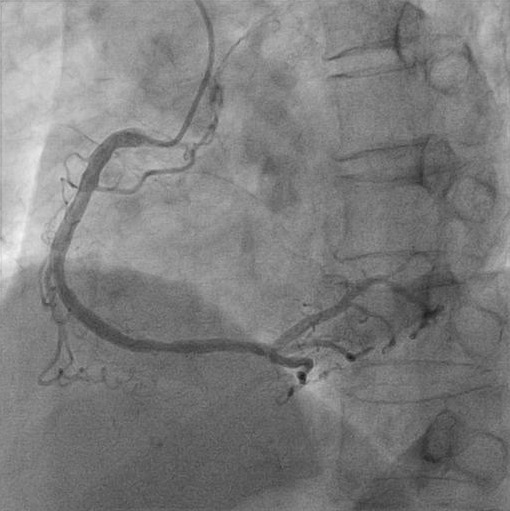

急性冠症候群の診断で緊急冠動脈造影検査が施行されました。右冠動脈に異常はありません。

冠動脈造影図

しかし、左冠動脈造影で、第一対角枝#9に90%、左冠動脈回旋枝鈍角枝#12に99%狭窄を認めました。

左冠動脈造影図

緊急冠動脈形成術(PCI)が行われ、同部位2箇所にステントが留置されました。

緊急冠動脈形成術(PCI)後の画像